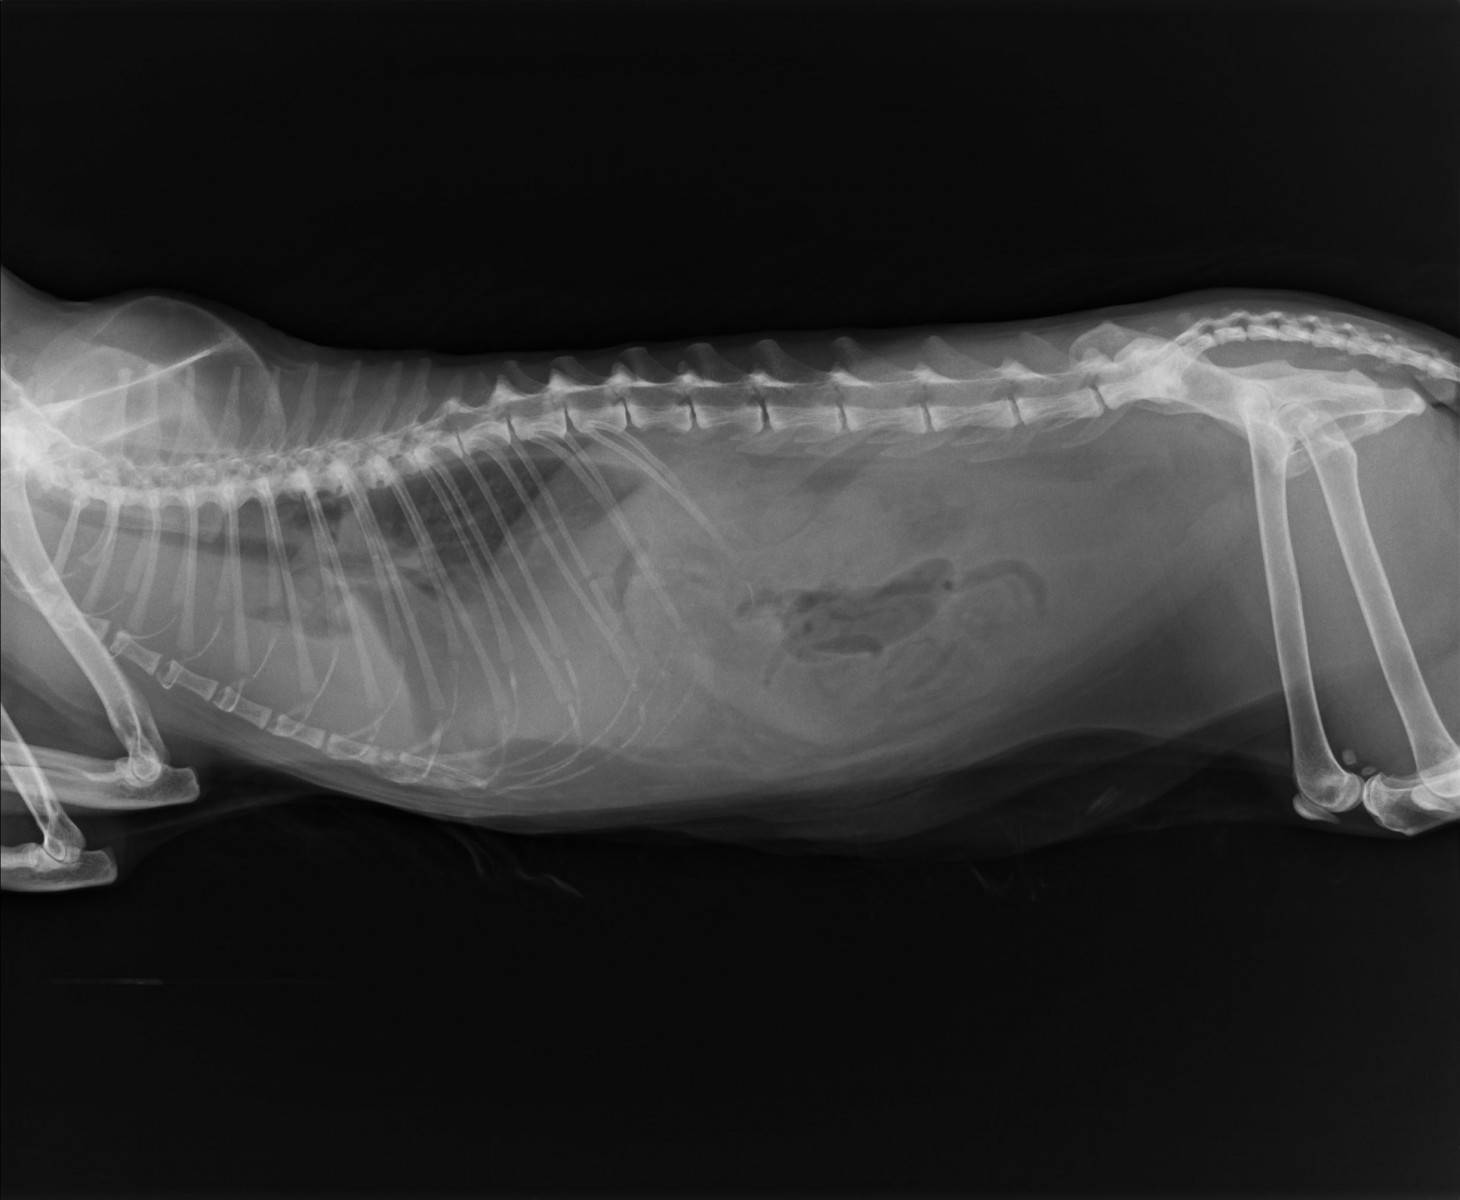

- рентген грудной клетки: позволяет выявить утолщение стенок бронхов, диафрагмальное растяжение, выявить образования в легких, исключить бронхит;

Диагностика астмы у кошек проводится путем рентген-исследования

| Инструментальные | Рентгенография грудной клетки | Оценка толщины стенок бронхов, состояния диафрагмы. При данном заболевании на рентгеновском снимке легкие прозрачные с выраженным рисунком. |

- рентгенографию грудной клетки;

Рентгенография покажет наличие воспаления в органах дыхания

Рентген легких кошки с астмой может показать отклонения, которые являются типичными для этого заболевания. Но данная процедура подходит не для всех. Да и чаще всего рентгеновское обследование назначается врачом только в том случае, если на его глазах повторились симптомы кашля, удушья, хрипов или других возможных проявлений астмы. А так как на первых порах заболевание может вызывать лишь эпизодические приступы, врач может просто их не дождаться, из-за чего порой упускается ценное для лечения время.

- Рентген грудной клетки, помогающий не только диагностировать астму (увеличение и утолщение стенок бронхов, диафрагмальное растяжение), но и исключить бронхит, образования в лёгких и прочие недуги системы дыхания.